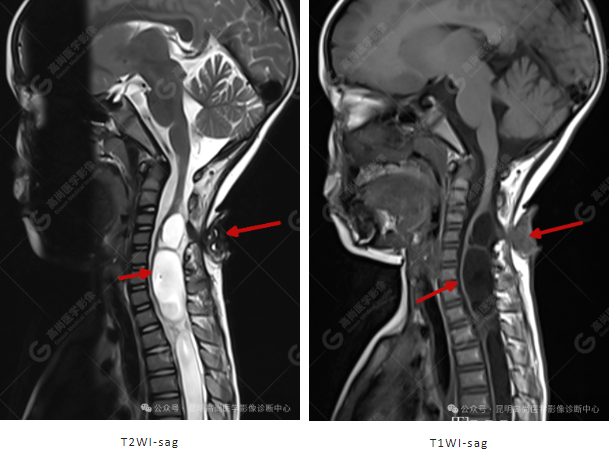

颈 3-5 层面颈后部软组织不规则片状异常信号影,脊膜膨出可能;颈 3、4 棘突局部显示不清;颈胸髓内(约颈 3-胸 9 椎体水平)异常信号影,考虑囊肿并局部颈髓空洞可能,肿瘤或其他待排;请结合临床及相关检查。